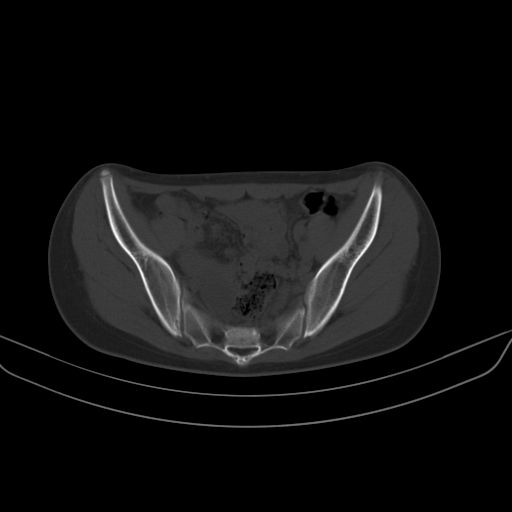

以下是引用zsl6918在2008-7-11 21:40:00的发言:[br]双侧骶髂关节骨质破坏以下三分之一为主,符合强直性脊柱炎表现

以下是引用zhangzhongshou在2008-7-11 21:41:00的发言:[br]患者是女性,hla-b27抗原(—),首先不太考虑强直性脊柱炎,建议查类风湿因子,骶髂关节改变考虑类风湿性关节炎可能性大,建议进一步检查。